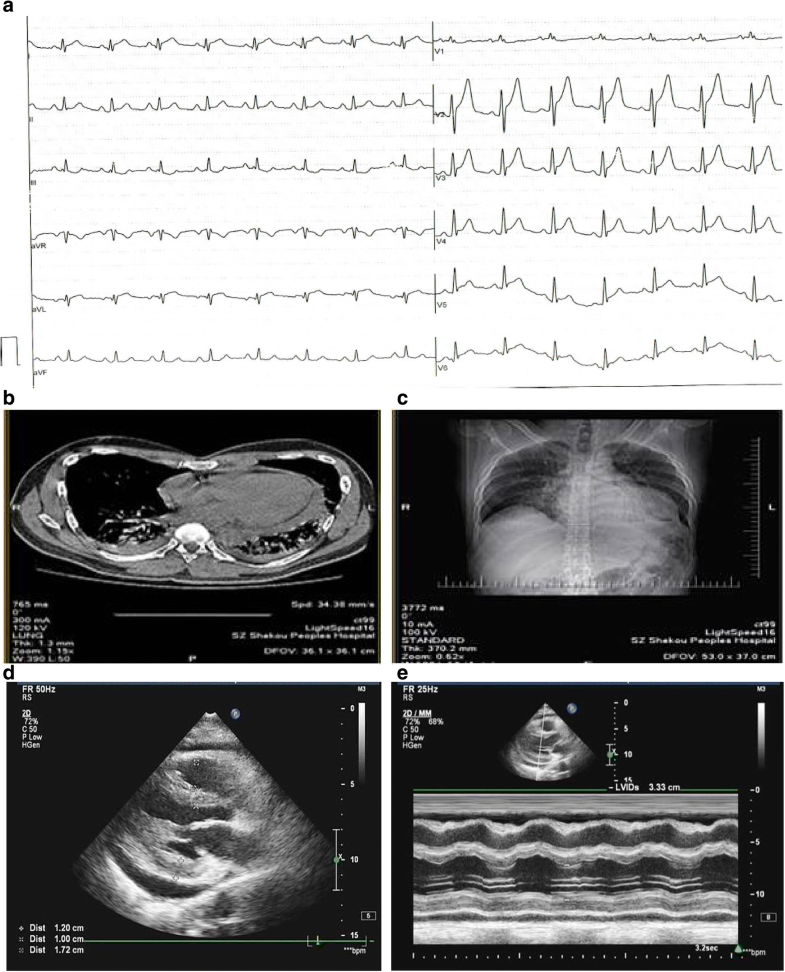

Multimodality imaging in patients with postcardiac injury syndrome Heart Post Cardiac Injury Syndrome Symptoms Auch erst nach monaten, zu perikarditis, perikarderguss, pleuritis,. Symptoms of dressler syndrome are likely to start weeks to a few months after a heart attack, surgery or injury to the chest. Post cardiac injury syndromes (pcis) are becoming increasingly common, due to the growing number of cardiovascular procedures. Dressler’s syndrome usually occurs within one to six weeks after heart surgery. Post Cardiac Injury Syndrome Symptoms.

Multimodality imaging in patients with postcardiac injury syndrome Heart Post Cardiac Injury Syndrome Symptoms Auch erst nach monaten, zu perikarditis, perikarderguss, pleuritis,. Diagnosis and management of persistent precipitating pathologies such as acute coronary syndrome (acs), pulmonary diseases, hemorrhage, sepsis, and various toxidromes. Post cardiac injury syndromes (pcis) are becoming increasingly common, due to the growing number of cardiovascular procedures. Symptoms of dressler syndrome are likely to start weeks to a few months after a. Post Cardiac Injury Syndrome Symptoms.

Multimodality imaging in patients with postcardiac injury syndrome Heart Post Cardiac Injury Syndrome Symptoms Diagnosis and management of persistent precipitating pathologies such as acute coronary syndrome (acs), pulmonary diseases, hemorrhage, sepsis, and various toxidromes. Dressler’s syndrome usually occurs within one to six weeks after heart surgery or a heart attack, but it can take up to several months for symptoms. Auch erst nach monaten, zu perikarditis, perikarderguss, pleuritis,. Post cardiac injury syndromes (pcis) are. Post Cardiac Injury Syndrome Symptoms.

Multimodality imaging in patients with postcardiac injury syndrome Heart Post Cardiac Injury Syndrome Symptoms Symptoms of dressler syndrome are likely to start weeks to a few months after a heart attack, surgery or injury to the chest. Diagnosis and management of persistent precipitating pathologies such as acute coronary syndrome (acs), pulmonary diseases, hemorrhage, sepsis, and various toxidromes. Post cardiac injury syndromes (pcis) are becoming increasingly common, due to the growing number of cardiovascular procedures.. Post Cardiac Injury Syndrome Symptoms.

Multimodality imaging in patients with postcardiac injury syndrome Heart Post Cardiac Injury Syndrome Symptoms Diagnosis and management of persistent precipitating pathologies such as acute coronary syndrome (acs), pulmonary diseases, hemorrhage, sepsis, and various toxidromes. Auch erst nach monaten, zu perikarditis, perikarderguss, pleuritis,. Post cardiac injury syndromes (pcis) are becoming increasingly common, due to the growing number of cardiovascular procedures. Dressler’s syndrome usually occurs within one to six weeks after heart surgery or a heart. Post Cardiac Injury Syndrome Symptoms.